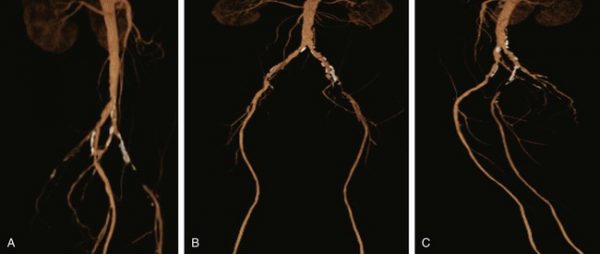

Ως ισχαιμία κάτω άκρων ορίζεται η μείωση ή διακοπή της ροής του αίματος στα κάτω άκρα λόγω κάποιας βλάβης ή απόφραξης στις αρτηρίες που το τροφοδοτούν. Πρόκειται για μία επικίνδυνη κατάσταση που ειδικά στα τελευταία στάδια της μπορεί να οδηγήσει ακόμα και σε γάγγραινα ή απώλεια του μέλους που πάσχει.

- Χρόνια στένωση των αρτηριών των άκρων η οποία προοδευτικά επιδεινώνεται και καταλήγει σε απόφραξη της αρτηρίας

- Η αρτηριακή εμβολή όπου θρόμβος πηγμένου αίματος από τη καρδιά μεταφέρεται με την κυκλοφορία στα

κάτω άκρα και αποφράσσει κάποια αρτηρία. Εμβολή μπορεί να έχουμε και από υλικό ανευρύσματος κοιλιακής αορτής ή λαγονίου ή ιγνυακής αρτηρίας (αθηροεμβολισμός)

κάτω άκρα και αποφράσσει κάποια αρτηρία. Εμβολή μπορεί να έχουμε και από υλικό ανευρύσματος κοιλιακής αορτής ή λαγονίου ή ιγνυακής αρτηρίας (αθηροεμβολισμός) - Θρόμβωση. Σε ήδη ανεπτυγμένη αθηρωματική πλάκα μιας αρτηρίας των κάτω άκρων αναπτύσσεται πάνω της θρόμβος, ο οποίος την αποφράσσει 100%